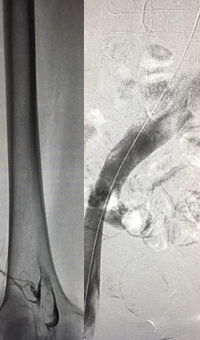

Case CLI with right foot ulcer thrombectomy: Posterior and anterior tibial

Case CLI with Right Foot Ulcer Thrombectomy pre-procedure arteriogram.

Arteriogram of posterior and anterior tibial post-CDT

PT and AT remained occluded following overnight CDT infusion of lytic

Case CLI with Right Foot Ulcer Thrombectomy post-AngioJet Solent Dista.

Post-AngioJet™ Solent™ Dista thrombectomy with PowerPulse™ delivery

AngioJet Solent Dista Catheter used in Power Pulse mode in both AT and PT. 30 min dwell in  AT and 45 min dwell in PT. Followed by Solent Dista Catheter used in thrombectomy mode

Case CLI with Right Foot Ulcer Thrombectomy post-procedure arteriogram.

Post-procedure arteriogram

Image following ballooning of small focal lesion in PT

Thrombectomy of occluded SFA

Thrombectomy of Occluded SFA - pre-procedure

Imaging SFA showing thrombus and calcification

Male in his late 40s presenting with pain in his right leg. An angiogram showed a total occlusion in the right superior femoral artery (SFA)

Thrombectomy of Occluded SFA - catheter positioning

Solent™ Proxi catheter positioned before the lesion

The physician delivered (antegrade) the Solent Proxi catheter to the proximal margin of the occlusion

Thrombectomy of Occluded SFA - thrombus removed

Thrombus removed following AngioJet™ treatment

After the third pass with Solent Proxi

Thrombectomy of Occluded SFA - post-adjunctive treatment

Post-adjunctive treatment

Final angiogram showing flow post-treatment

Results from case studies are not necessarily predictive of results in other cases. Results in other cases may vary.